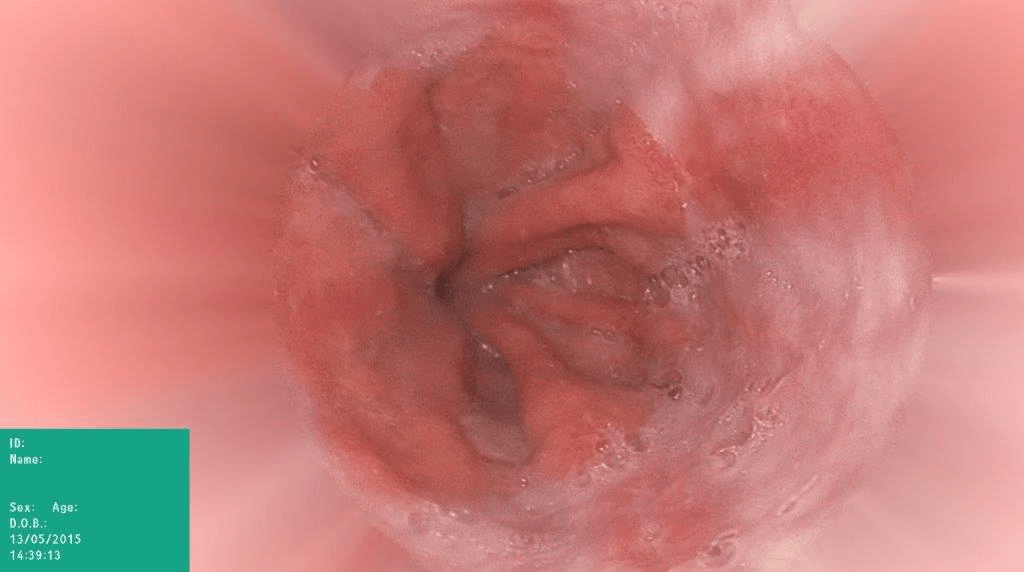

Refer to caption

(a) No abnormality

(b) Polyp

(c) Oesophagitis

(d) Ulcerative Colitis

Figure 1: Illustrations of question-answer pairs along with common abnormalities in gastrointestinal image from ImageCLEFmed-MEDVQA-GI-2023 dataset

The new dataset released for the ImageCLEFmed-MEDVQA-GI-2023 challenge is based on the HyperKvasir dataset [29], the largest gastrointestinal collections with more than 100,000 images, with the additional question-and-answer ground truth developed by medical collaborators. The development set and test set include a total of 3949 images from different procedures such as gastroscopy and colonoscopy, spanning the entire gastrointestinal tract, from mouth to anus. Each image has a total of 18 questions about abnormalities, surgical instruments, normal findings and other artefacts, with multiple answers possible for each, as shown in Table 1. Not all questions will be relevant to the provided image, and the VQA system should be able to handle cases where there is no correct answer. Figure 1 depicts several examples of question-answer pairs on common abnormalities in gastrointestinal tract, such as Colon Polyps, Oesophagitis, and Ulcerative Colitis. As shown in Figure 1(d), there are three possible answers to the question "What color is the abnormality?": "Pink," "Red," and "White", and a typical VQA system should be able to identify all three colors. In general, the image may contains a variety of noise and components that locates across abnormalities, such as highlight spots or instruments, which pose a significant challenge in developing efficient VQA systems for gastrointestinal domain.